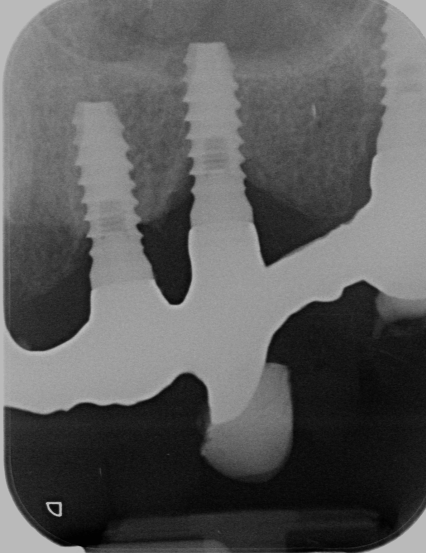

Buenos días, tenemos este caso, para hacer una sobredentadura, la paciente nos llega así porque su clínica de origen ha cerrado y los aditamentos que nosotros tenemos no son compatibles, [...]